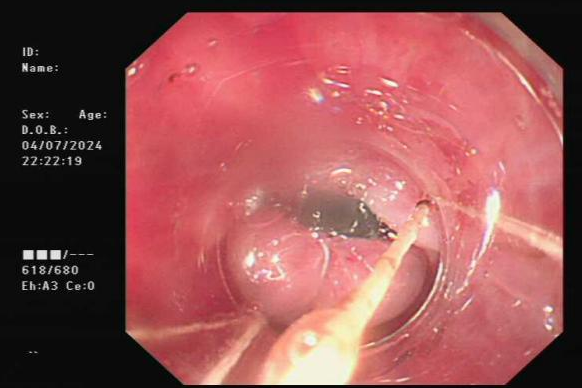

陈XX,女性,79岁,因“反复呕血黑便1年余,再发2小时”入院,既往有食管胃底静脉曲张破裂出血病史,入院血常规提示血红蛋白84g/L。患者入院后经药物对症治疗仍反复呕血,考虑有活动性出血。消化内科团队行急诊胃镜检查,提示食管胃底静脉曲张,食管近贲门静脉曲张活动性出血,随即为患者行经内镜食管静脉曲张出血套扎术,术后观察无活动性出血,对症治疗后患者已出院。

食管近贲门静脉曲张破裂出血

套扎曲张静脉后出血停止